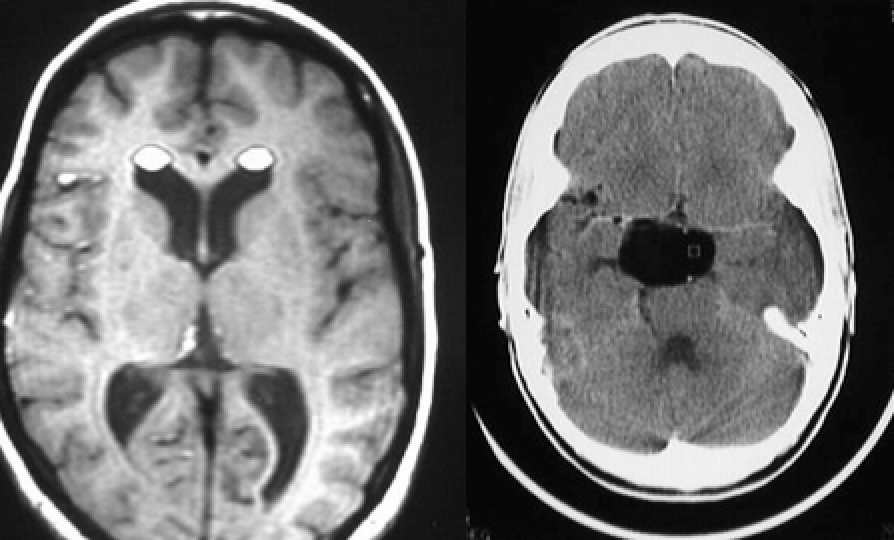

17 yo with new partial seizures

Diagnosis?

Other differential diagnoses?

Ganglioglioma

Faint hypointense T2 FLAIR signal without significant mass effect or edema

Bright gyriform enhancement on T1

Can also be cystic or calcified

When these occur in the cerebellum=Lhermitte-Duclos Disease

Differential: DNET, gangliocytoma, oligodendroglioma, focal encephalitis

Man with sleep apnea

Clival chordoma

Abnormal isointense T1 signal mass involving the entire clivus

Contains physaliphorus cells

Other Differential: Metastasis, lymphoma, multiple myeloma